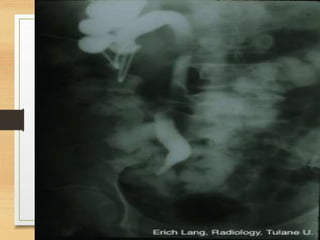

Radiological

• KUB

CASE 2

• A 35-year-old man presents to the emergency

department with intermittent right loin to groin pain

and visible hematuria. He had history of passing

stones . What is the likely cause?